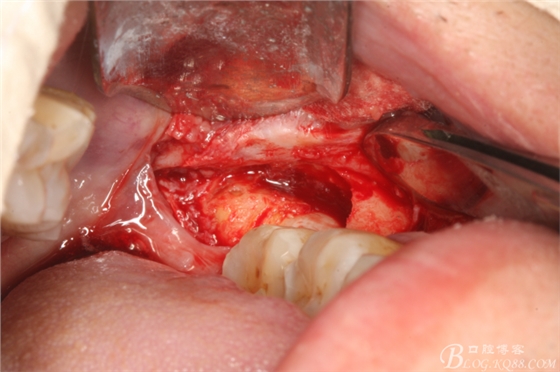

圖2.切開、翻瓣、去骨